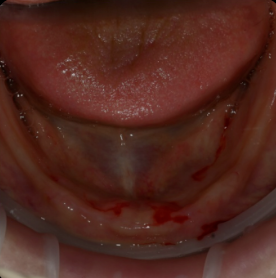

틀니가 잘 빠지고 불편해서 고민이세요?

예전으로 돌아가고 싶으신가요?

갈비도 뜯고.. 입가에 주름도 없고 팽팽하던 그때로...

혹시 당신 혹은 부모님의 이야기인가요?

많은 분들의 걱정,

디지털 풀아치가 해결해 드립니다